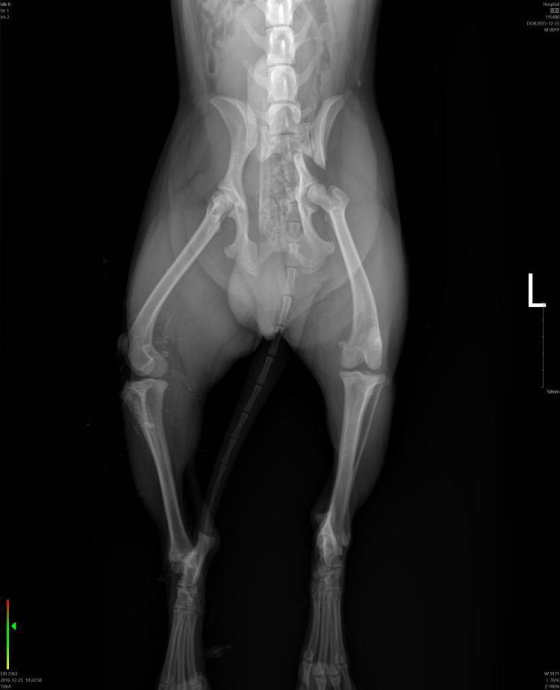

犬骨盆骨折内固定

犬骨盆骨折,多数情况是由于车祸导致,此图中的骨折犬就是 由于未拴犬链,被汽车撞伤,导致左侧髂骨体骨折,右侧见髂关节脱位,术后两个月恢复正常做了,所以动物主人遛狗时一定拴好犬链。